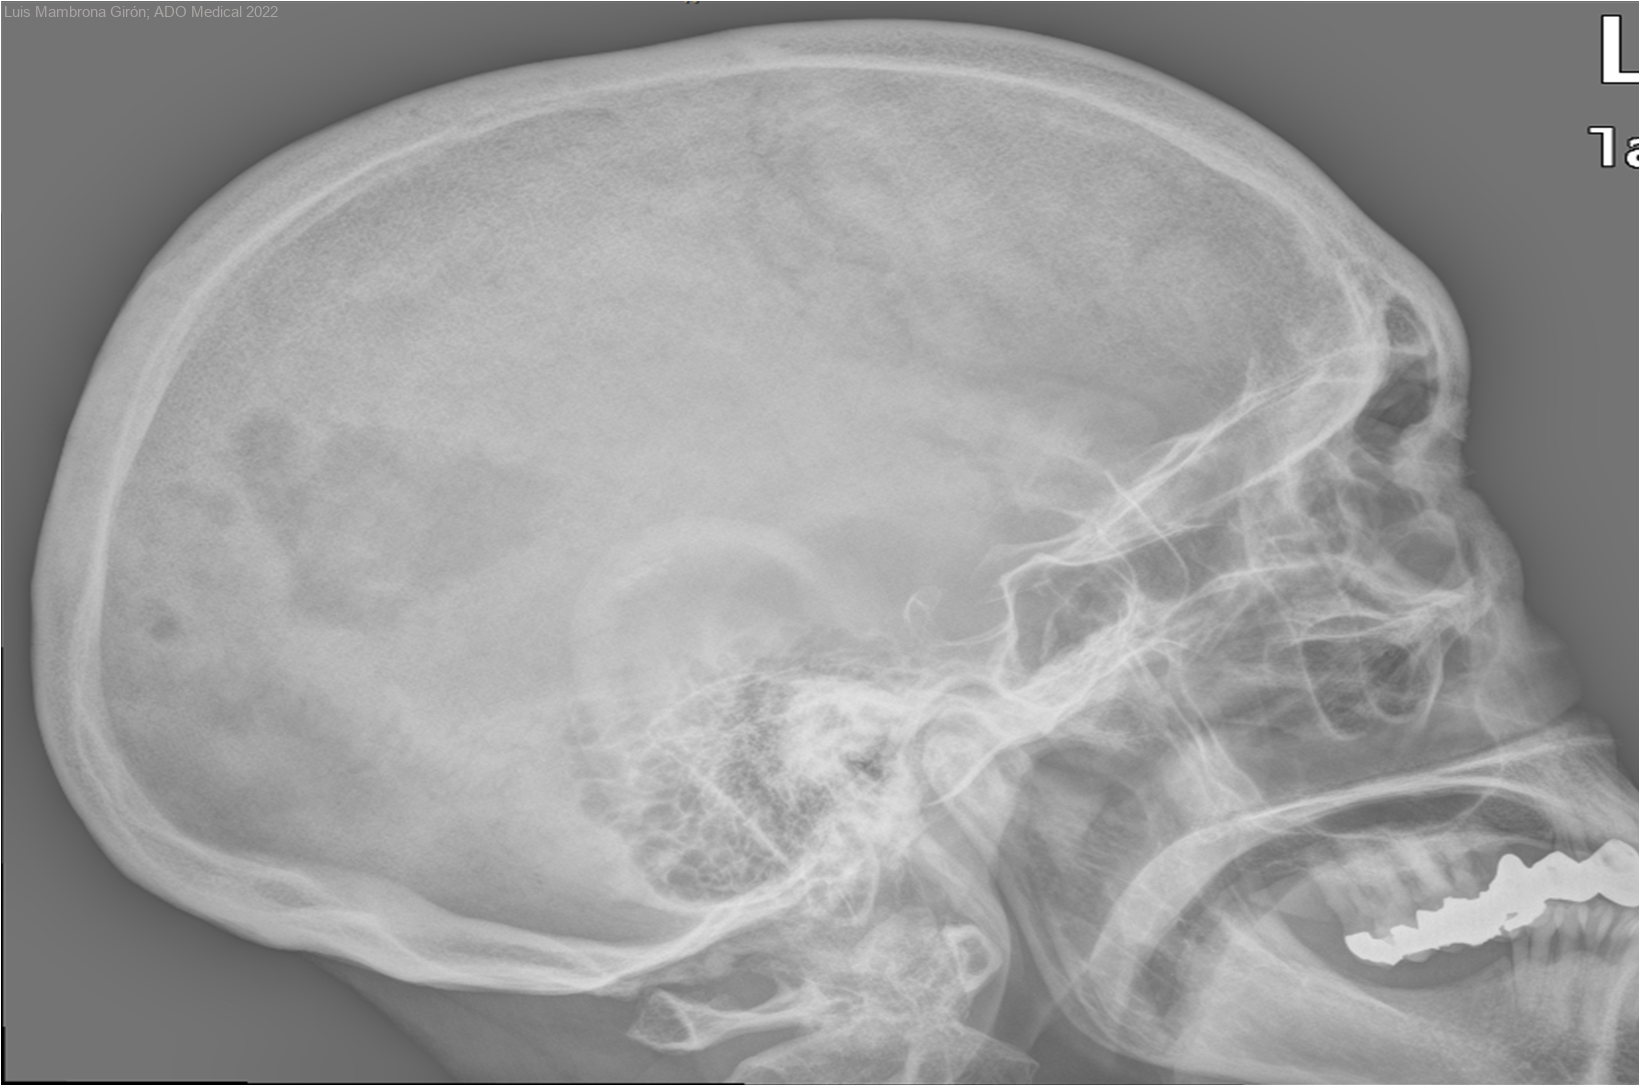

Metástasis múltiples óseas

Mujer de 55 años que acude a la consulta externa de Rehabilitación tras ser remitida por el Médico de Atención Primaria para valorar tratamiento por deterioro funcional en contexto de cuadro neoplásico con metástasis.